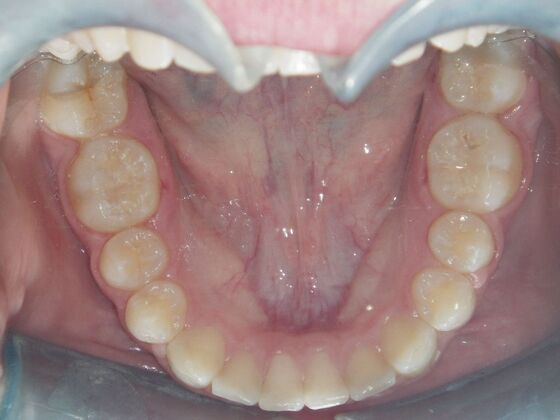

Orthodontics: Case 2

Description

Patient is 9 years old and presents with 100% overbite and blocked out upper and lower lateral incisors. Both upper central incisors are palatally inclined causing a lack of space available for most anterior teeth. Advised her parents that she needs Phase I Interceptive Orthodontic treatment to provide room for all upper and lower front teeth. Phase I treatment was begun and finished, then began Phase II treatment shortly thereafter to finalize case. Removable retainer were fabricated for retention.